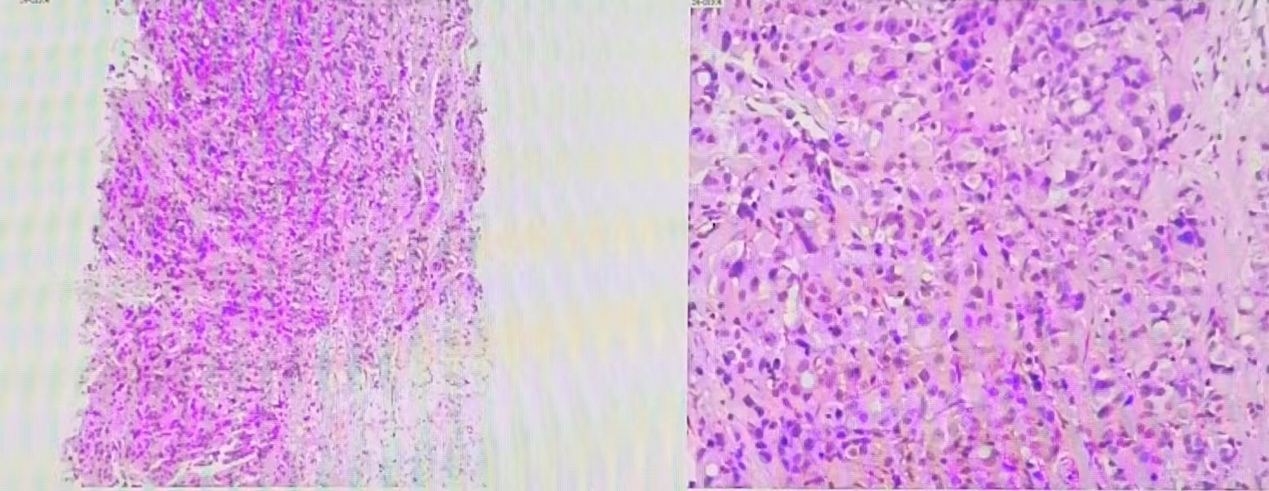

穿刺病理结果(2024年05月22日 我院):

图 穿刺病理结果(2024年05月22日 我院)

(左乳11点结节)浸润性癌。

(左侧腋窝淋巴结)可见癌转移。

免疫组化结果:ER (90%,+++), PR (80%,+++), Ki67(40%+), CK5/6(-), P63(-), E - cad (+), P120(膜+), AR (+), EGFR (-), Her-2(0), GATA3(+), CK14(-), GCDFP -15(+)。

穿刺病理结果(2024年05月24日 我院):

图 穿刺病理结果(2024年05月24日 我院)

(右侧胸壁结节)穿刺组织内见条索样、腺样排列的肿瘤细胞,细胞具有异型性,结合病史及免疫组化表型,符合乳腺癌转移。

免疫组化结果:Ckpan(+),GATA3(+),GCDFP-15(+),ER(90%,+++),PR(80%,+++),Her-2(0),Ki67(30%+),S100(-),Mammaglobin(-),Myogenin(-),MyoD1(-),Vimentin(-)。